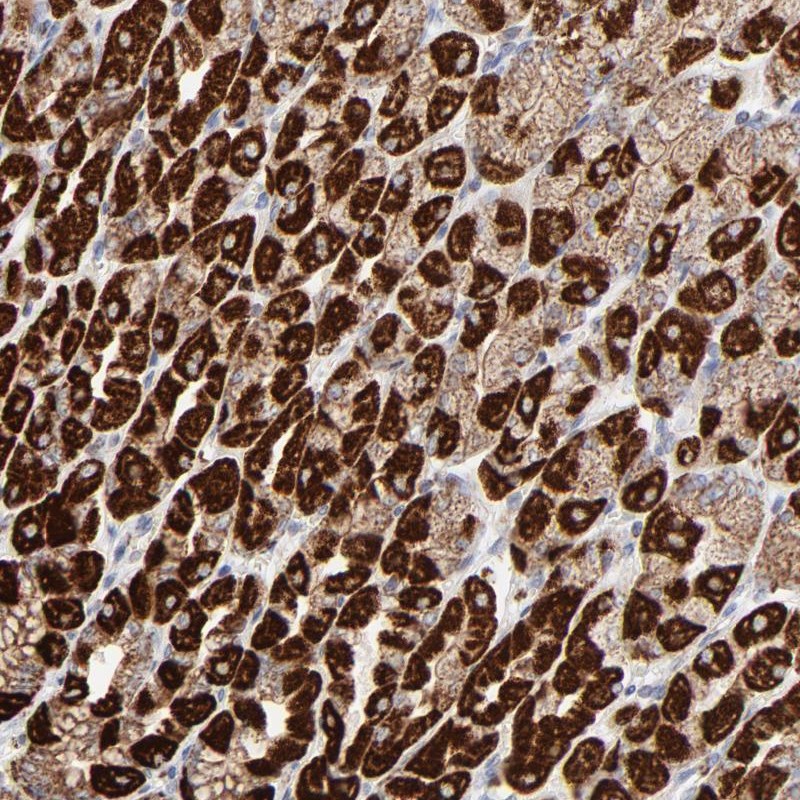

Immunohistochemical staining of human stomach shows strong cytoplasmic positivity in glandular cells.